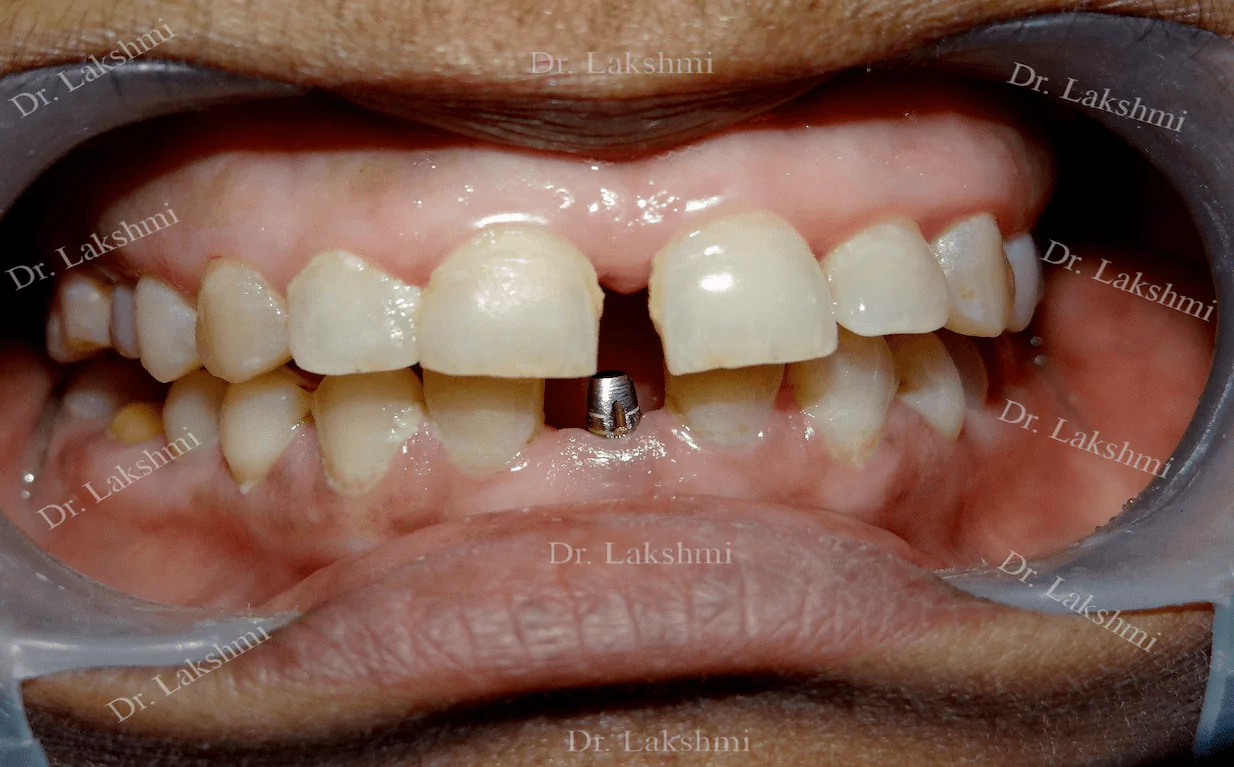

Requires the placement of a single dental implant (either 2 stage or 1 stage) in the region of the missing tooth, followed by a crown (artificial tooth) over

Treatment Duration: 2 stage dental implants: The replacement is completed in 2 stages which are spread over an interval of minimum 3 months. The first stage involves the placement of the implant and requires one to two sittings,Temporary Crowns will be given to the patient. The second stage involves the placement of the artificial tooth (Permanent crown).

1 stage dental implant: Requires just one stage for the placement of the implant and crown(Permanent Crown).